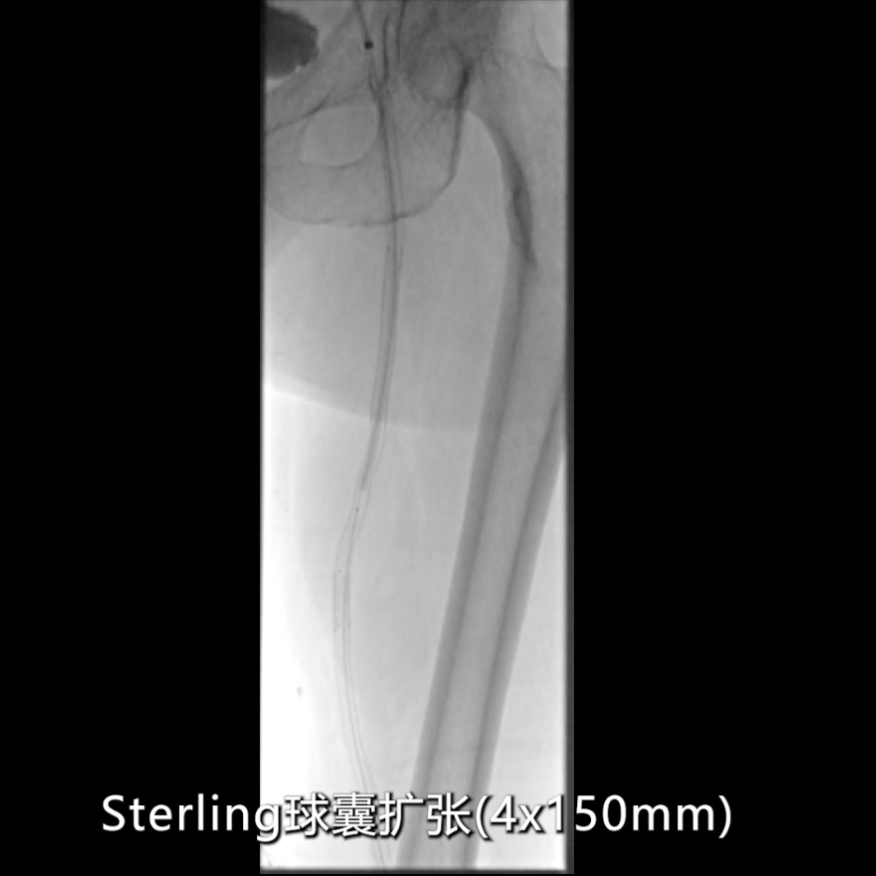

球囊扩张成形

初步扩张:使用4×150mmSterling球囊,由近及远扩张整个支架段及远端病变(考虑合并P1段病理性改变);

在影像图下发现在在支架远端有一定的局部狭窄。